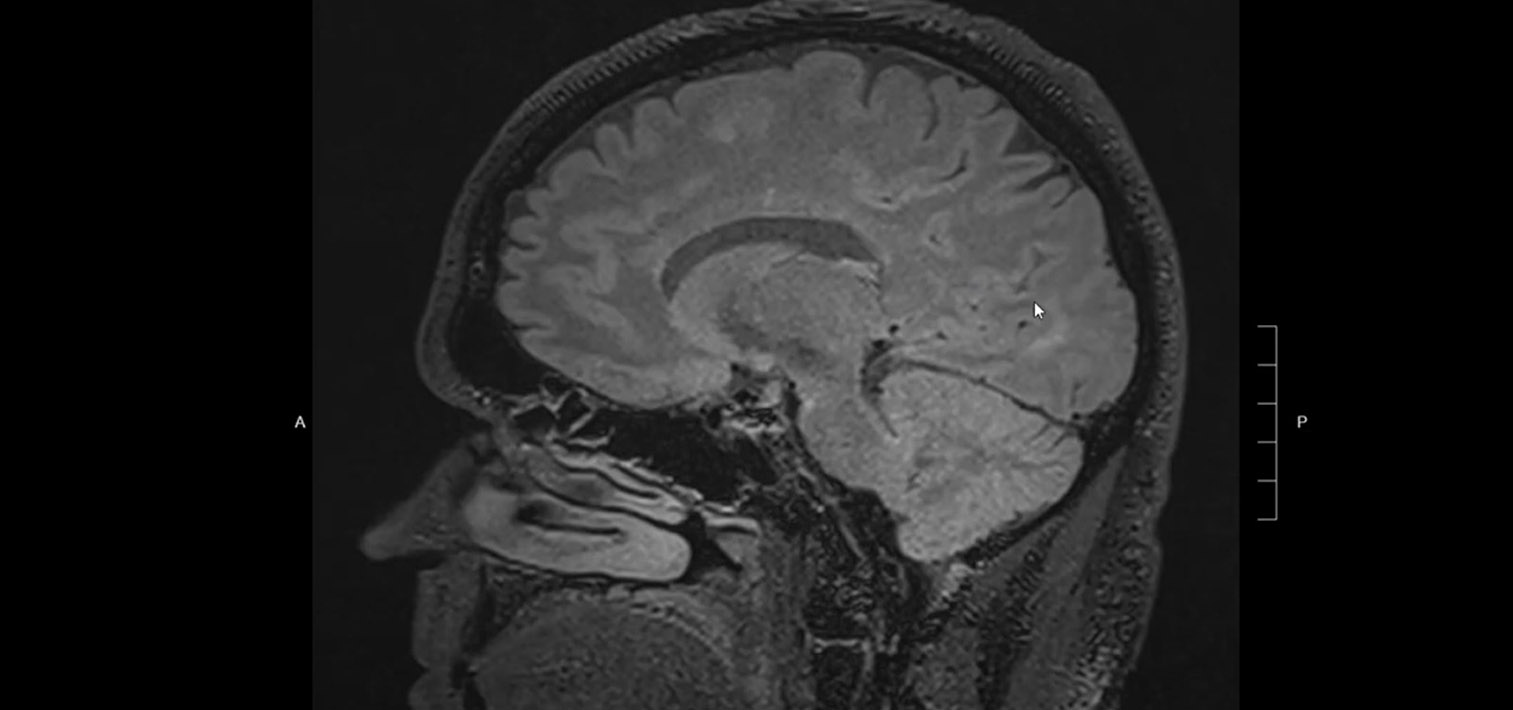

What does MS (Multiple Sclerosis) look like on brain MRI? Avoid wrongful diagnosis!

Dr. Elahi briefly discusses typical MRI findings in multiple sclerosis (MS) and how these findings can be differentiated from non-MS findings such as in small vessel ischemia or migraine pathology. Characteristics of MS lesions help avoid misdiagnosis and/or over-diagnosis of MS in patients who may be suffering from other disorders.